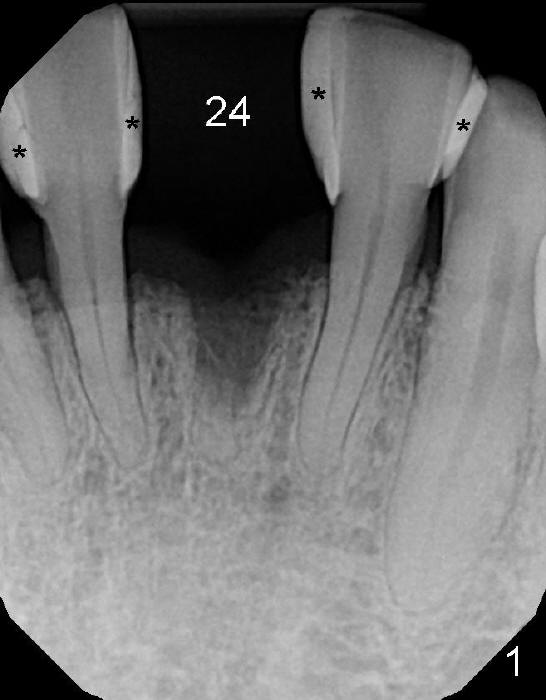

A 60-year-old man requests restoration of a missing lower central (Fig.1: #24). His diabetes is controlled by med. The edentulous space is wide mesiodistally; the diastemata between the adjacent teeth are closed by composite (*). The tooth was extracted 2-3 years ago due to trauma.

To place the implant correctly, the preop PA should be studied carefully to find the divergence of the roots of the neighboring teeth (Fig.1). The depth of the initial osteotomy should be shorter, for example, 11 mm instead of 14 mm. Once the trajectory is found to be corrected, an incision should be made; the osteotomy is to be overcorrected with Lindermann bur (Fig.8 black); the whole osteotomy is changed with proper angulation (Fig.9 arrows).

Fig.10,11 show 7 day follow up. The permanent crown is seated 4.5 months postop (Fig.12). Minimal bone resorption occurs at the crest 4 months postop (Fig.13), which is most likely associated with conservative approach (flapless). The patient returns for follow up 2.5 months post cementation (Fig.14,15). The implant remains in the bone 4 years post cementation (Fig.16 CT coronal section; lingual thread exposure, corresponding to preop defect in Fig.1). There is mild coronal bone resorption 5 years 4 months post cementation (Fig.17).